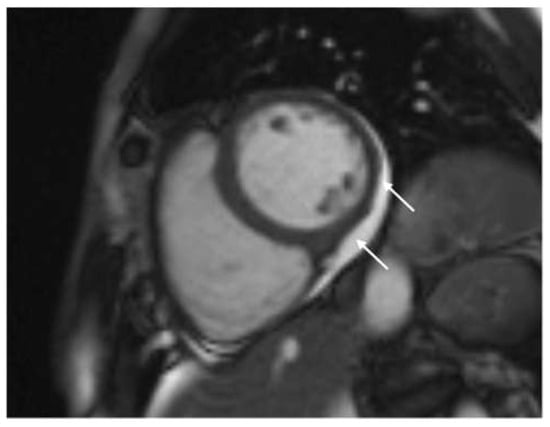

| LGE, n (%) | 67 (78.8) |

| Distribution of LGE, n (%) | |

| Subepicardial | 27 (31.8) |

| Mid-wall | 7 (8.2) |

| Transmural | 1 (1.2) |

| Subepicardial and mid-wall | 32 (37.6) |

| Late pericardial enhancement, n (%) | 34 (40.0) |